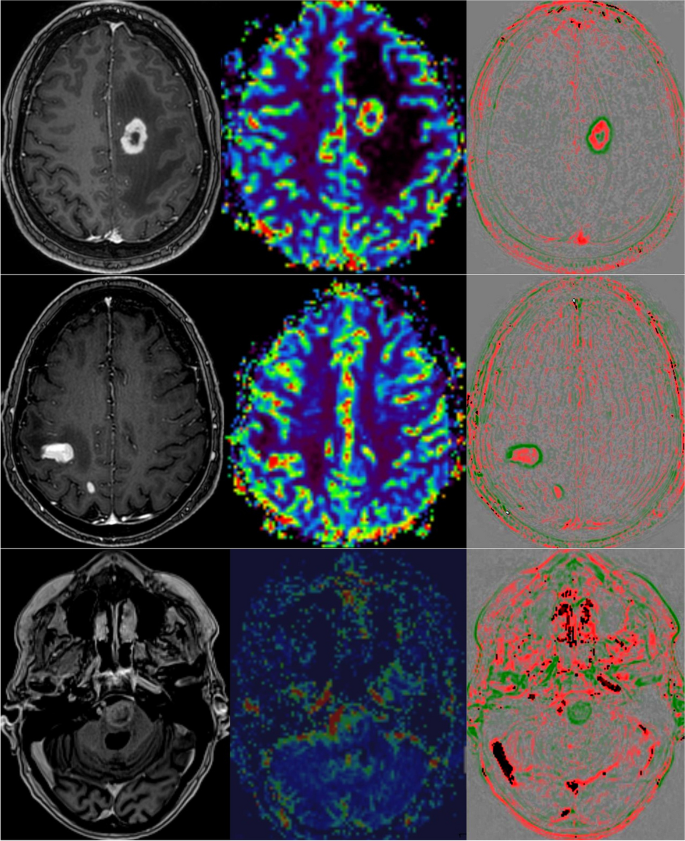

Области снижения интенсивности wash-out (красные) коррелируют с активной опухолевой тканью (рис.4), области повышения интенсивности wash-in (зеленые) — с некрозом или фиброзом (рис.5).

Рис.4. Примеры первичного диагноза (вверху: глиобластома; в центре: лимфома ЦНС; внизу: метастазы в головной мозг мелкоклеточной карциномы легкого). Слева: Т1-взвешенные изображения с усилением контраста; средняя карта rCBV МР-перфузии; Справа: карта быстрого вымывания.

Рис.5. Оценка терапии глиобластомы. Вверху: 200% прогресс объема за 6 недель наблюдения. МР-перфузия (средняя) не показала локальной гиперперфузии. Быстрое вымывание (справа) выявило участки повышенного быстрого вымывания (красный). Середина: Типичные посттерапевтические изменения без гиперперфузии и вымывания, но смываемые (зеленые). Внизу: Лучевой некроз (3-месячное наблюдение было стабильным) с менее активными опухолевыми клетками с пузырчатым видом небольших контрастных поражений и минимальной гиперперфузией (стрелка), а также минимальными кольцеобразными вымывами с красной точкой (стрелка). Слева: Т1-взвешенные изображения с усилением контраста; средняя карта rCBV МР-перфузии; Справа: карта быстрого вымывания.